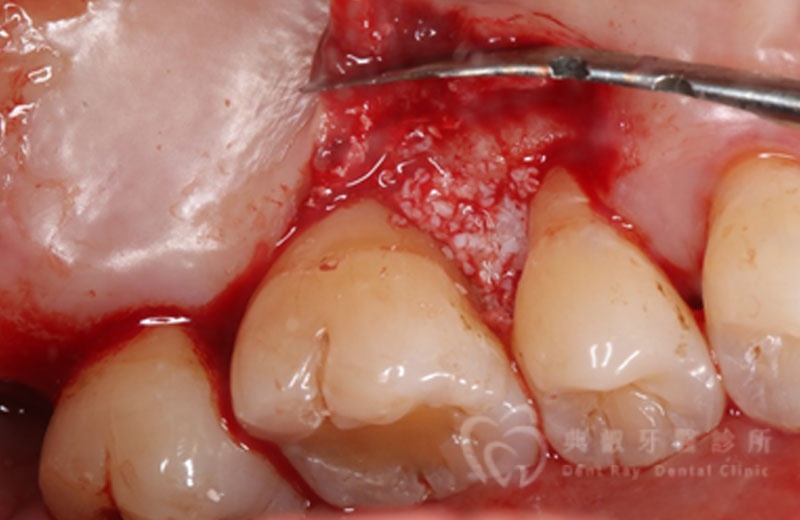

牙周手術案例三

術後六個月